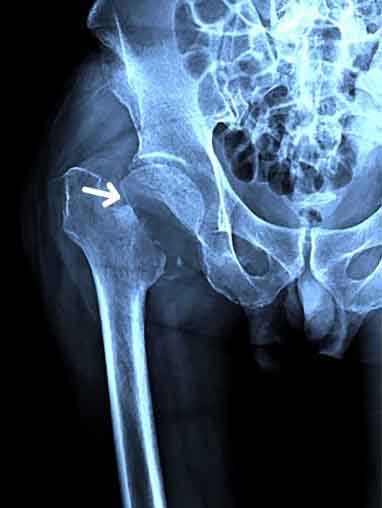

Abb. 1: Röntgen. Schenkelhalsfraktur re. (präoperativ).

Erstkontakt im Rahmen eines FLS (Fracture Liaison Service) auf der unfallchirurgischen Abteilung. Das FLS-Team wurde aufgrund einer rezenten Schenkelhals-Fraktur einer 83-jährigen Frau nach Sturz zu Hause informiert. Die chirurgische

Versorgung mittels Hüft-Total Endoprothese erfolgte bereits am Vortag.